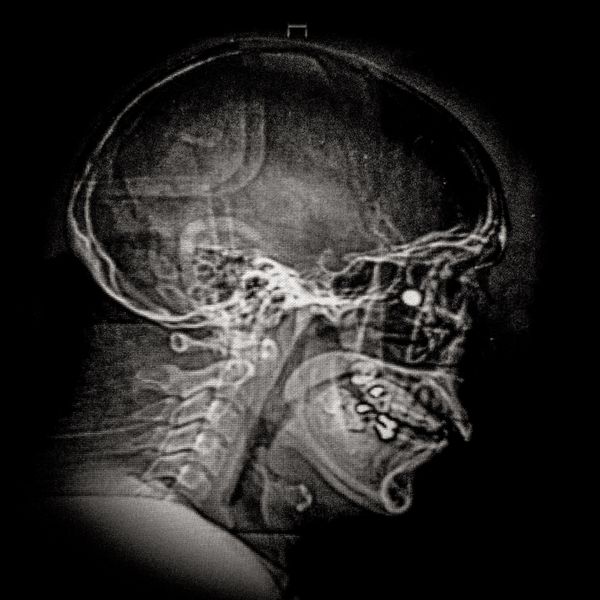

X ray showing the embedded pellet of Camilo Galvez (24) injured by chilean police during Santiago protests.